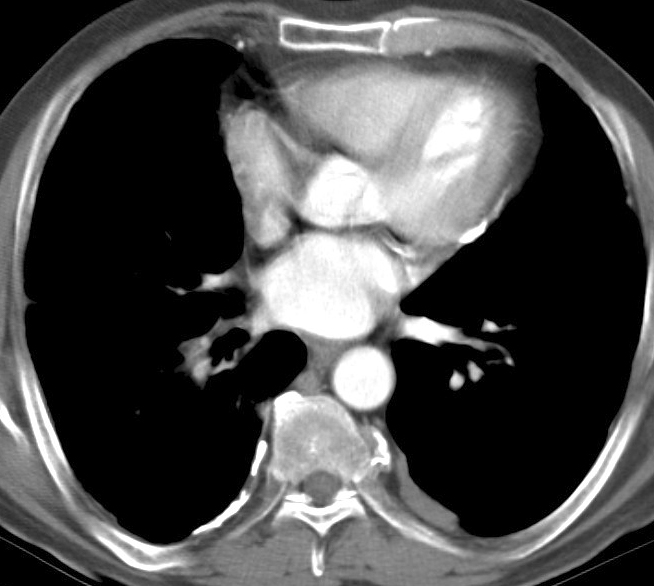

Asbestos 2 CTa

Date: 06/02/2004